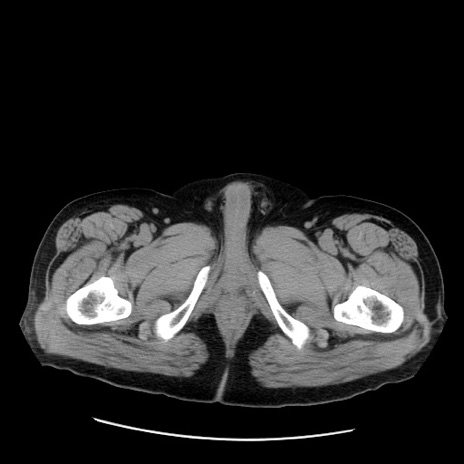

症例20(横断像)

【症例】 60歳代男性

【主訴】 腹部膨満、嘔吐

【現病歴】5日前頃より倦怠感を認め食事量減少し4日前の朝嘔吐、食事摂取困難となった。 3日前近医受診し点滴施行され整腸剤などを処方された。 当日他院を受診し、腹部膨満著明、炎症反応の上昇(CRP10.8、WBC11200)あり、紹介受診となる。

【身体所見】 意識JCS1 受け答えがはっきりしないBP 111/57mHg、 P 67bpm、、BT35.2°C、SpO2 97%(RA)、 腹部:膨隆、打診で鼓音あり、全体的に圧痛有り、腸蠕動音(-)、反跳痛ははっきりせず。

【データ】WBC 11400、CRP 14.20